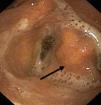

Lesion mechanismsTranslaryngeal intubation can affect the laryngeal structures as a result of direct impact during intubation, in the course of prolonged intubation, in restless patents, as a consequence of abrasion of the laryngeal mucosa, or secondary to the mere presence of the tube orotracheal. Common findings are vocal cord edema, as well as swelling of the supraglottic space (Fig. 1), with a less frequent observation of granulomas at this level. Other infrequent findings are arytenoid subluxation or luxation (Fig. 2), or vocal cord paralysis secondary to direct damage or involvement of the recurrent nerves. All these lesions adversely affect swallowing.10,11

Instrumental testsFibroscopyTransnasal fibroscopy is able to visualize the laryngopharyngeal structures and their possible alterations. During the test a functional evaluation is made, including direct visualization of the formation of the food bolus (liquid or solid) in its pharyngeal phase, together with laryngeal tests to assess vocal cord adduction and cough reflexes.33–39

After swallowing, fibroscopy moreover allows the detection of retained food in the hypopharyngeal region (supraglottic recesses), and its visualization in the airway in the case of tracheal aspiration.36–38

Studies of this kind should be carried out by experienced specialists, and their sensitivity can be improved if the swallowed substances are stained with easily identifiable dyes. Despite such measures, however, the procedure involves significant interobserver variability39,40 (Fig. 3).